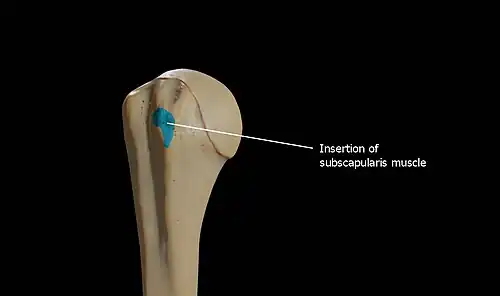

Above and in front it presents an impression for the insertion of the tendon of the subscapularis.